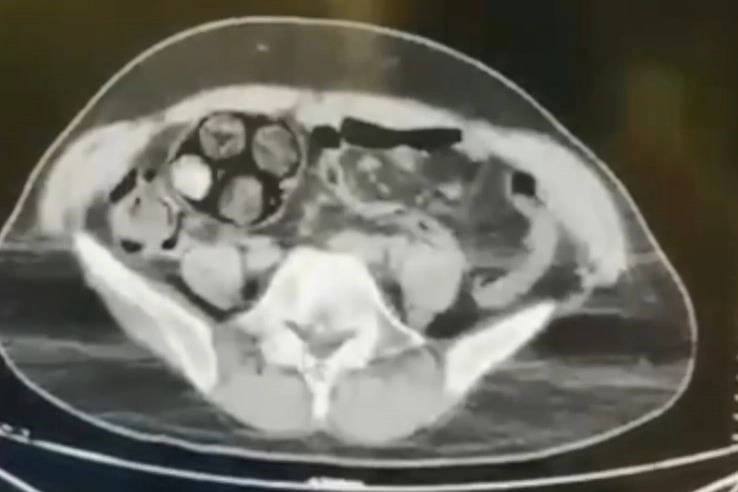

Edinilen bilgiye göre, Artvin İl Jandarma KOM Şube Müdürlüğü ekipleri, İran uyruklu Farshid Rafıeıeınsheykh (43) adlı şüphelinin 8 Mart tarihinde vücudu içerisine uyuşturucu madde gizleyerek Artvin’e getireceği bilgisi üzerine çalışma başlattı. Yapılan takip sonucu Artvin merkez Çayağzı Mahallesi’nde yakalanan şüphelinin üst aramasında herhangi bir suç unsuruna rastlanmadı. Bunun üzerine şüpheli, Ceza Muhakemesi Kanunu'nun 75. maddesi gereği iç ve dış beden muayenesi için Artvin Devlet Hastanesine sevk edildi. Çekilen tomografi sonucu zanlının bağırsaklarında 10 paket tespit edildi. Cerrahi müdahale ile çıkarılan paketlerin içinde toplamda 350 gram metamfetamin maddesi olduğu belirlendi. Gözaltına alınan İranlı zanlı hastanede müşahede altına alınırken, olayla ilgili soruşturma başlatıldı.